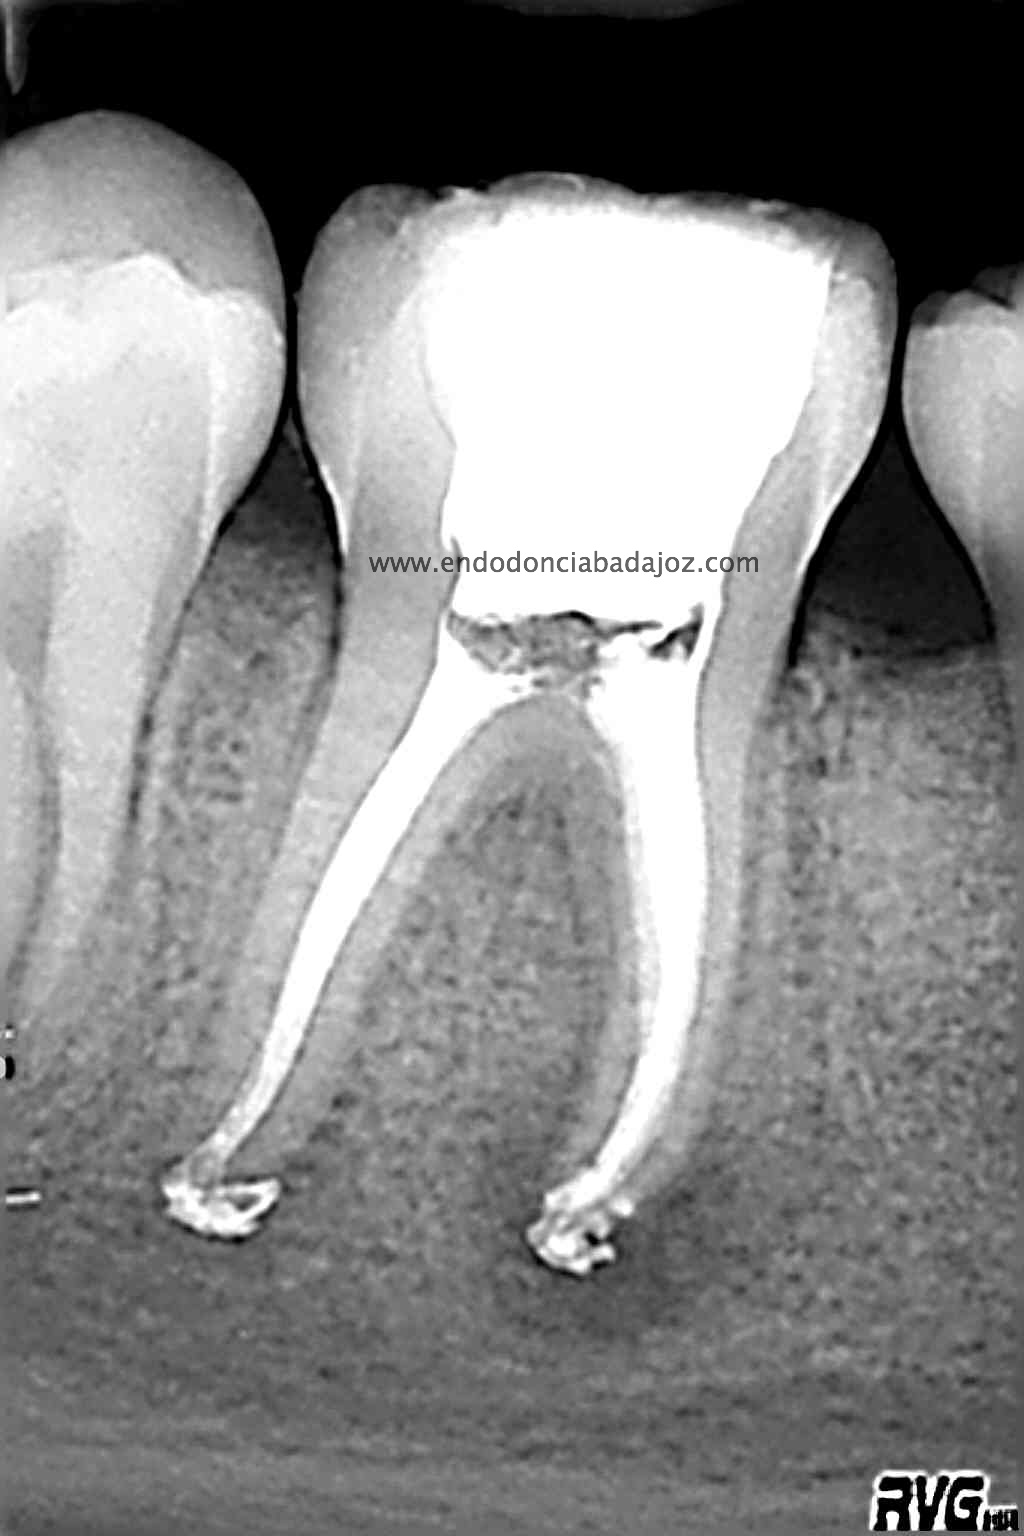

Una vez que hemos limpiado los conductos con un sistema de instrumentación  Protaper en combinación con limas K3. Pasamos a obturar los mismos con una técnica de condensación vertical de ola contínua de Buchanan y un backfilling con la gutapercha inyectada de la pistola ObturaII. Tomamos varias proyecciones, orto-mesio-distal

Con estas tres proyecciones nos quedamos mucho más tranquilos y seguros de un buen sellado hermético y tridimensional des sistema de conductos de esta pieza.